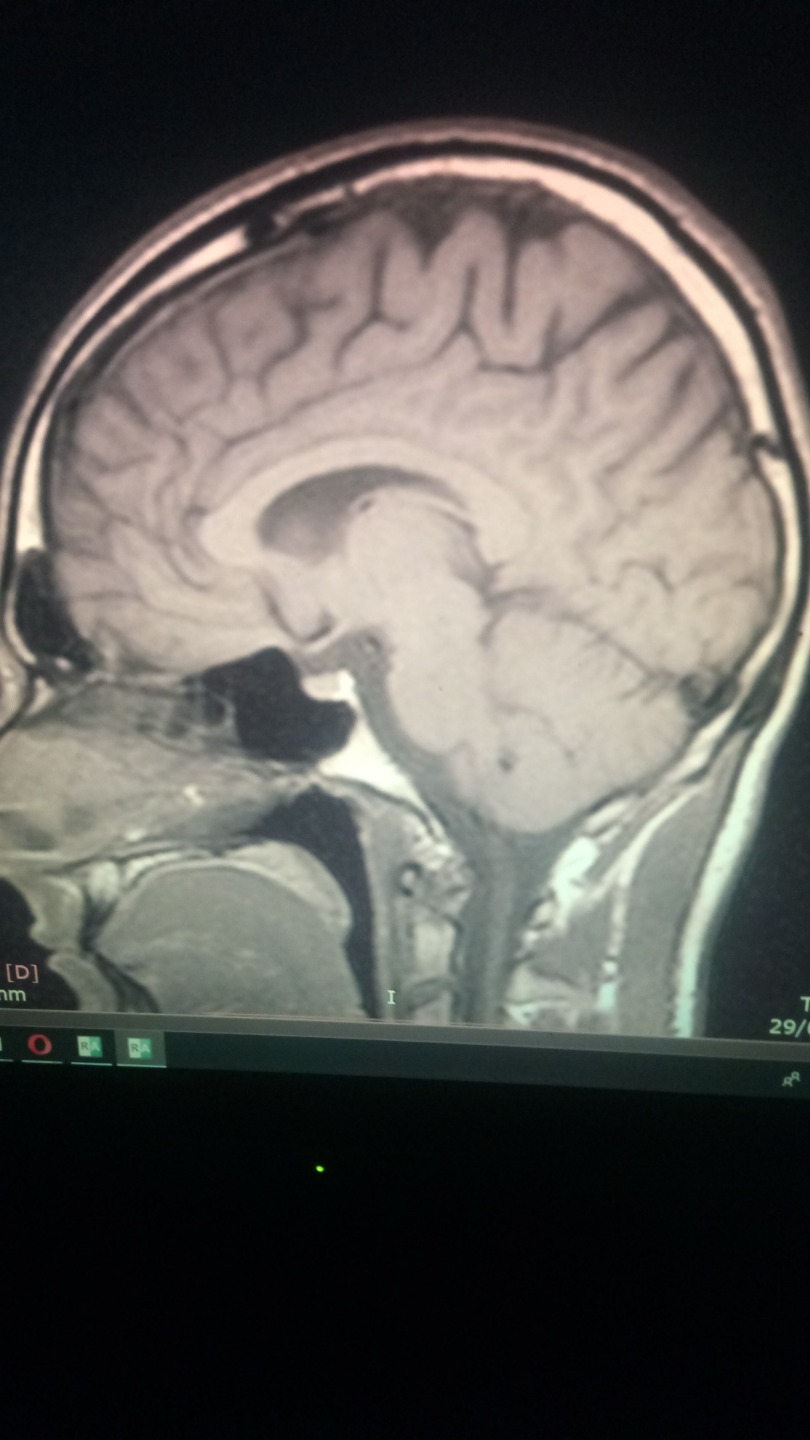

PD : Will atach a photo of my brain, if anyone knows how to read mri scans and know what is going on on my brain is real apreciated. I just think is a infection that somehow is cicatrized thanks to mms.

Neurologist says I have nothin, I dont believe him.

the infection ( look at the pics of my brain mri, i had not headaches, nor nothing, but my brain was having an infections, i noticed something was wrong because i had insomnia for 3 months , like real hardcore insmonia, visual snow, poor memory and concentration, joint paints, dificulti breathing (babesia like simptom) coughfin, and stuff like that. But it wasnt like a normal type of cold. It was weird. I got headeaches when I started to take mms, specially big doses of 15 drops. less than that and standart protocol 1000 was not effective.